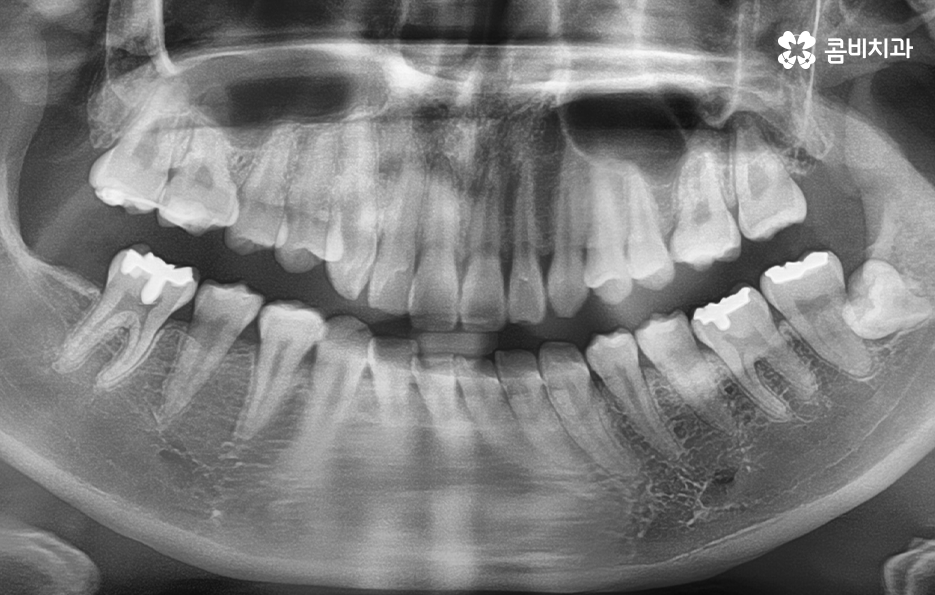

사랑니 발치하면 다들 비슷한 고민을 할 거 같지만 좀더 자세히 들여다 보면 사랑니의 형태가 정말 다양하고 누워있는 사랑니 마저도 그 위치나 자라는 방향, 각도 등이 환자분들마다 천차만별이라는 점도 알게 되실 거예요

정상적으로 맹출된 사랑니가 아닌 사진에서 보시는 사랑니의 케이스처럼 어금니 부분으로 완전히 누워있는 사랑니의 경우에는 늦지 않게 발치 계획을 세우시길 권하고 있습니다

사랑니 발치에 대해 시점이 중요한 이유 중에 하나는 어금니와 인접하기 때문에 정상적인 위치와 방향으로 맹출된 사랑니라도 청결관리 문제로 인해 어금니에도 악영향을 주는 사례가 많기 때문인데 누워있는 사랑니의 경우에는 청결관리와 무관하게 어금니 손상을 일으키는 경우가 많기 때문에 미리 예방적으로 발치를 권하는 경우가 많이 있어요

사랑니 하면 어떤 사랑니든지 언젠가는 문제가 될 수 있겠지만 그중에서도 위 사진에서 보여지는 누운 사랑니의 정도라면 그 시점이 3,40대 전후에도 문제가 커질 수 있다는 점에서 최소한 경각심을 갖고 문제가 커질 수 있음을 먼저 인지하시고 대학병원 혹은 사랑니를 전문적으로 발치할 수 있는 치과에서 치료 계획을 세우시길 권하고 있어요